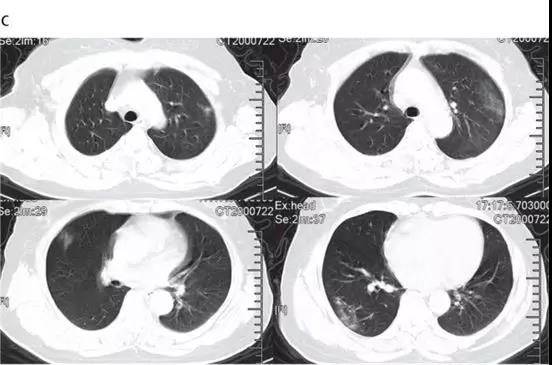

隨后的胸部CT顯示雙側(cè)毛玻璃樣混濁,而實變消除(見下圖)。